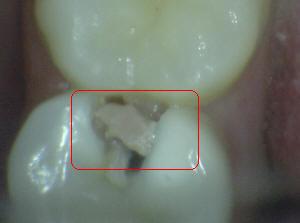

Sistema Internacional para la Detección y Evaluación de Caries (ICDAS)

¿Determine los códigos pertinentes a cada imagen?

Click en el hipervínculo: Para comparar el resultado de su diagnóstico